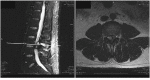

Initial lumbar spine sagittal magnetic resonance images performed 3 months prior to presentation. The T2-weighted image shows a hyperintense cystic mass at the L2-L3 dorsal epidural space.

Second lumbar spine magnetic resonance imaging three months after the initial imaging. T2-weighted sequence shows a heterogeneous hyperintense cystic mass at the L3-L4 dorsal epidural space and the initial cystic mass at L2-3 level has resolved.